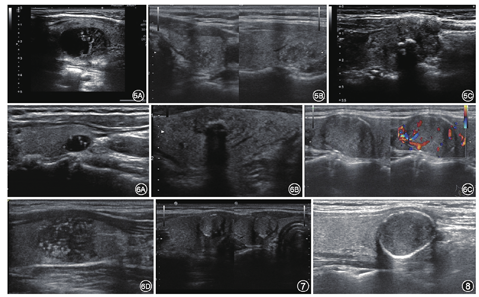

边缘光滑是大部分结节性甲状腺肿的特征(图5A);边缘模糊(图5B),即难以辨认结节与周围甲状腺实质的界限;分叶或不规则指的是结节的边缘呈针刺状、锯齿状或呈锐角突出于周围实质,上述特征分别给予0分、0分、2分。ACR委员会认为声晕的存在对于鉴别甲状腺结节良恶性意义不大,因此忽略声晕的存在,没有给予分值。

甲状腺外侵犯(extrathyroidal extension,ETE)分为广泛或微小[13](图5C)。广泛ETE的特点是结节广泛侵犯邻近的软组织和(或)血管结构,是一个高度可靠的恶性肿瘤标志。当超声检查发现结节在甲状腺边缘向外凸出或甲状腺被膜回声连续性中断时,高度可疑有ETE[14]。对此种情况,我们的做法是分三种情况描述:结节距前/后被膜的距离、紧邻被膜或被膜连续性中断,以此帮助临床医生选择治疗方案。

由于TI-RADS版本较多,不同单位使用的分级系统不统一;通过ACR TI-RADS分级的实际应用,认为此分级还有需要完善的地方,未来可以将彩色多普勒超声、弹性成像等技术纳入分级;对某些指标详尽分类,比如边缘钙化的完整性与不完整的分值(图7,图8);对未分化癌、淋巴瘤、恶性滤泡性肿瘤等有价值的分类;ACR TI-RADS分级评估为恶性结节的活检率高于其他指南,而活检为恶性结节的百分比低于其他指南[19],这可能会导致临床的过度诊断。ACR TI-RADS分级是一种对结节进行评分分级的方法,仅对结节进行分级,远远不能满足临床需求,对结节良恶性的鉴别要综合判断,建议超声医生首先进行分级,然后在此基础上提出可能性诊断。